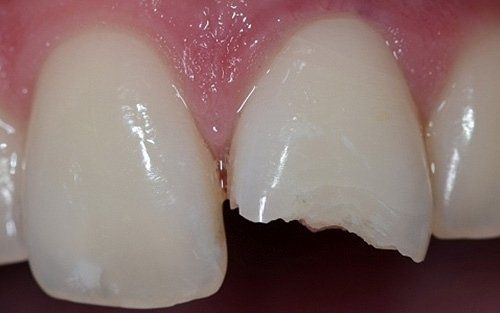

I denti da latte traumatizzati più spesso vanno incontro a necrosi con conseguente cambiamento di colore, divenendo grigiastri, segno della morte delle cellule della polpa dentaria. In altre occasioni, il dente può fratturarsi in maniera più o meno ampia: se il frammento viene ritrovato, potrà essere re-incollato in maniera invisibile, oppure verrà ricostruito con i materiali compositi.